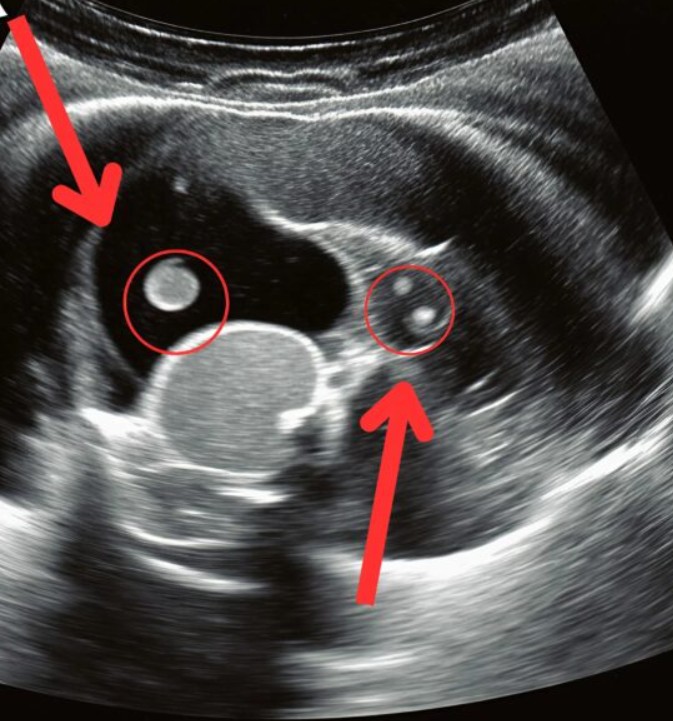

Hastanenin koridorlarında zaman adeta donmuş gibiydi. Kızım sedyede acı içinde kıvranırken, doktorların endişeli bakışları altında ultrason sonuçlarını bekledik. Sonunda doktor yanımıza geldi ve hiçbir ebeveynin duymak istemediği cümleyi söyledi: “Pikat leikkaus on tarpeen.” Meğer o sırt ağrıları sandığımız gibi çantadan değil, sessizce büyüyen bir böbrek taşından kaynaklanıyormuş. Taş yerinden oynayıp kanala düşmüş, şiddetli sancı ve hayati risk yaratıyormuş.